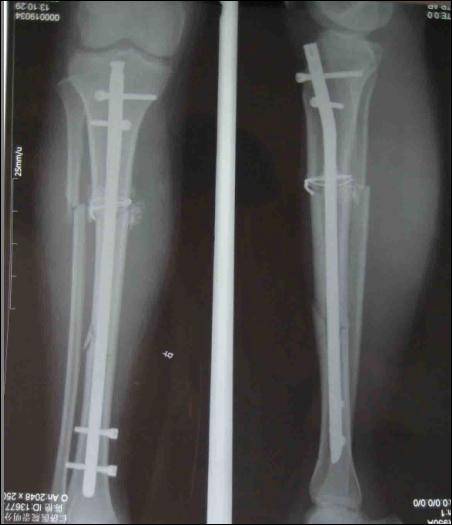

孩子脛骨骨折為何被打入鈦釘

被打入鋼釘?shù)氖疽鈭D